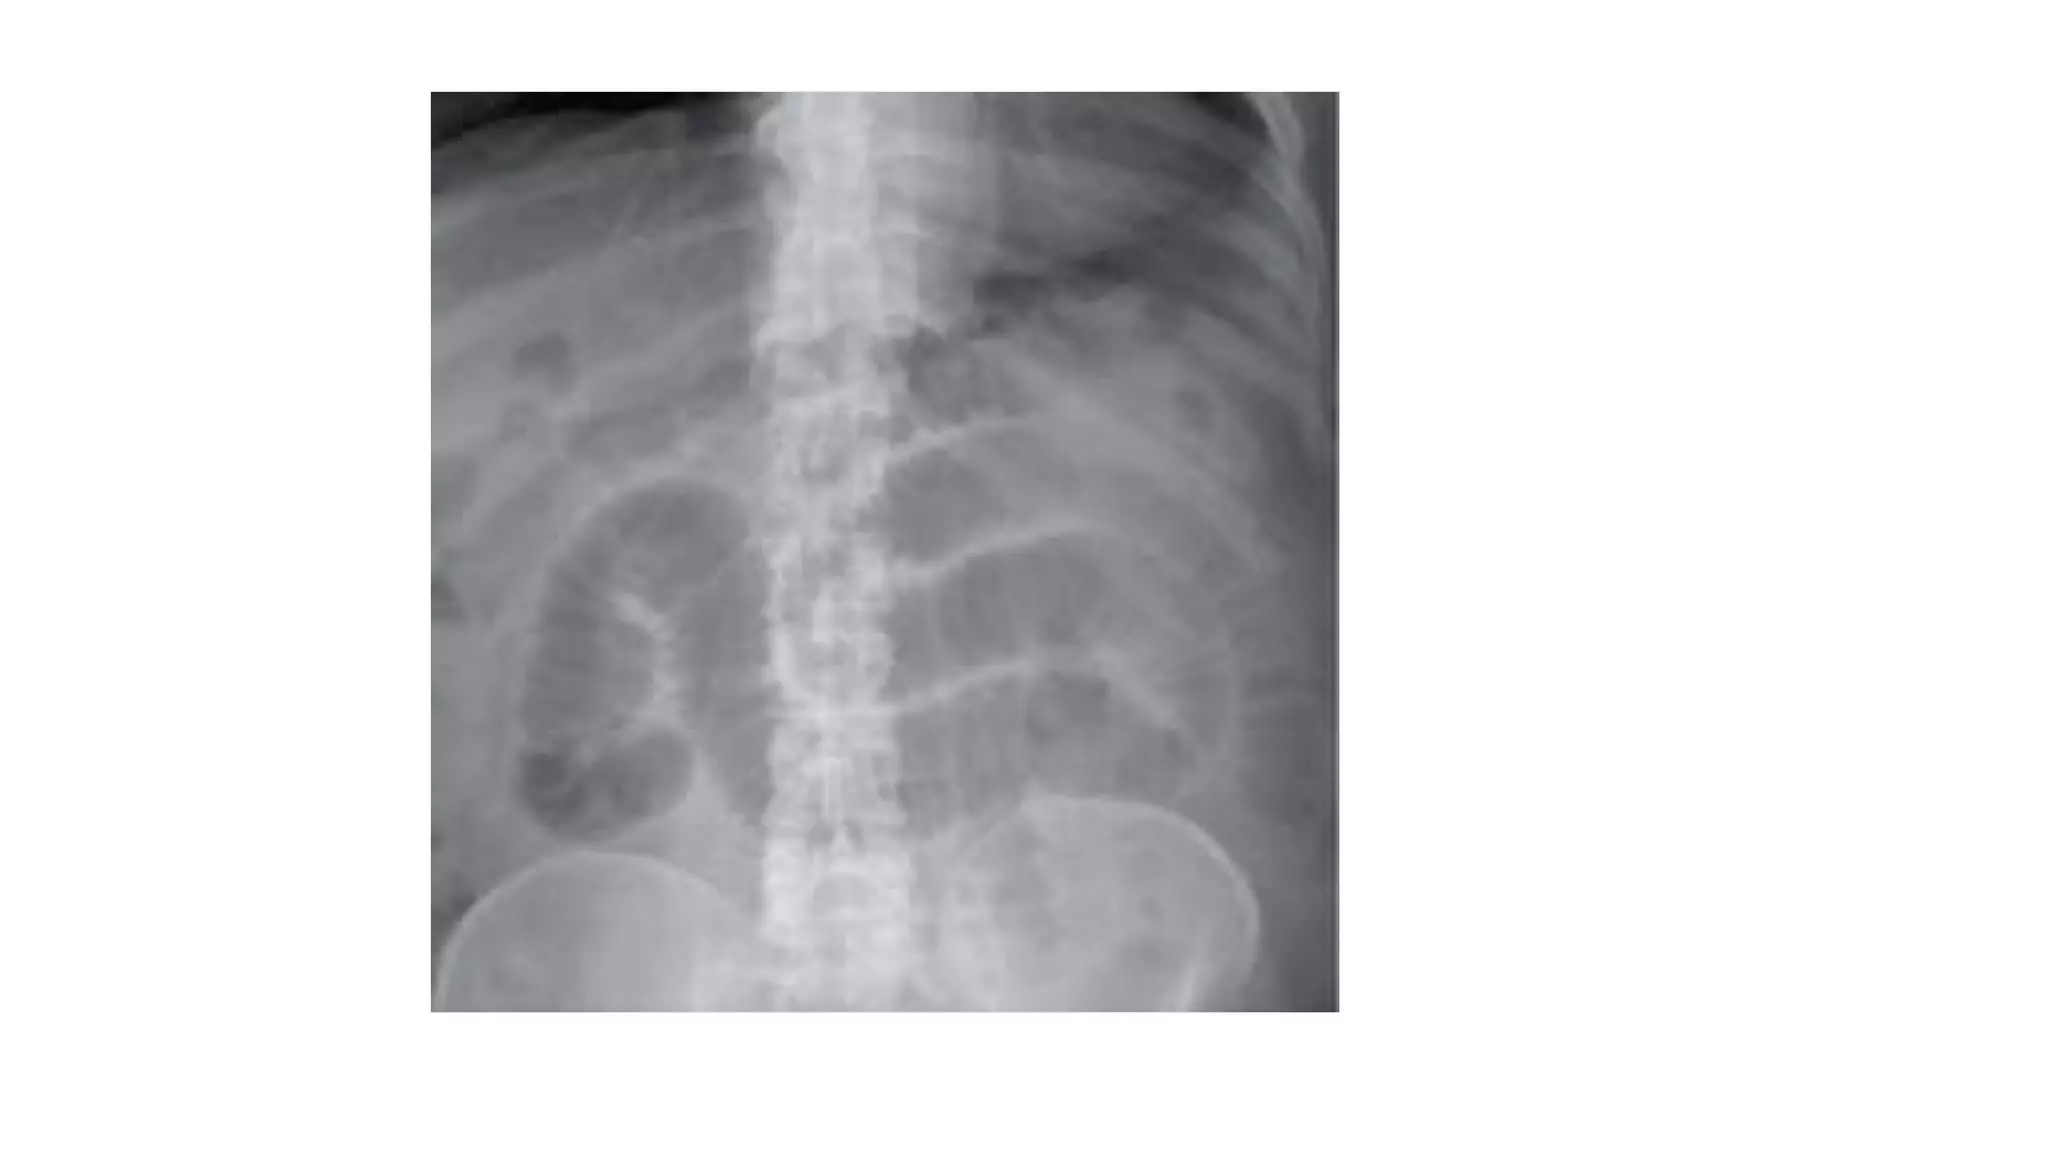

Plain abdominal radiography

distended gas-filled loops of

small and large intestine.

Air-fluid levels may be seen

 Under some circumstances, it may be difficult to distinguish ileus from partial

small bowel obstruction. ►

CT scan may be useful to

exclude mechanical

obstruction, especially

in postoperative patients.